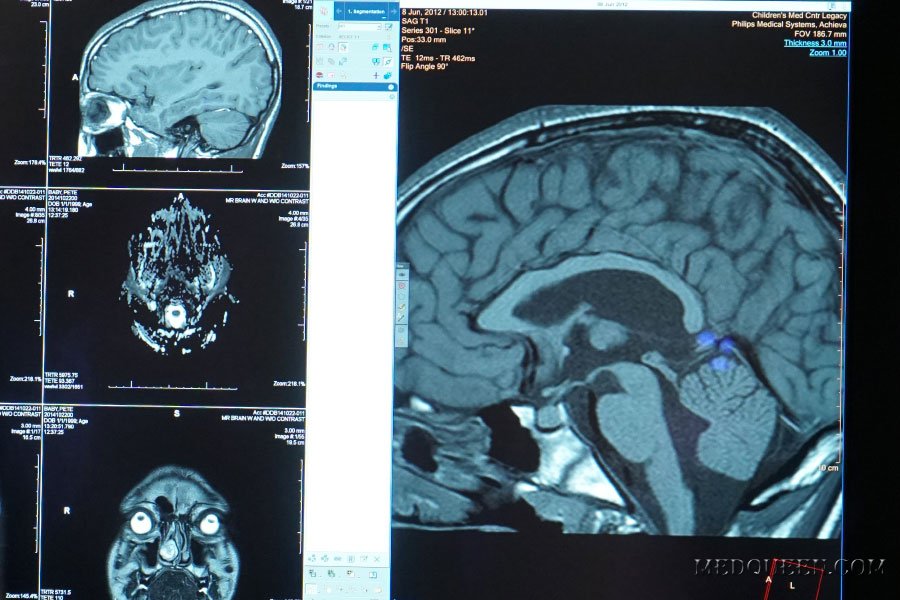

ДиагностикаМагнитно-резонансная томография сосудов головного мозга и шеи (МР-ангиография) — современный высокоточный метод обследования сосудов, системы кровообращения зоны интереса с построением ее детализированной цифровой 3D-реконструкции. Уникальность МРТ заключается в простоте, безопасности и отличной проникающей способности электромагнитного излучения. Сканирование головного мозга позволяет увидеть, не нарушено ли кровообращение в связи с закупоркой какого-либо жизненно-важного сосуда, имеются ли опасные аневризмы и опухоли, а также узнать, какие участки головного мозга (структуры лимбической системы, гипоталамус, спинной мозг и др.) подвержены нарушению трофики или другим негативным изменениям в связи с патологиями артерий и вен.

МРТ сосудов головного мозга показывает все вышеперечисленные патологии головного мозга, а также врожденные и приобретенные отклонения в развитии (дегенеративные изменения) структур кровообращения головного мозга и шеи.

Визуальная оценка сосудов позволяет исключить аневризмы и тромбы, которые в перспективе могут привести к сосудистой катастрофе — ишемическому или острому геморрагическому инсульту. По данным ВОЗ, распространенность данной патологии, способной привести к летальному исходу, за последние 30 лет выросла на 70%! Однако и выявляемость инсульта, качество оказываемой медицинской помощи тоже выросло, что в числе прочего связано с развитием современных диагностических методов МРТ и КТ. Эксперты связывают рост распространенности инсультов с такими факторами как гиподинамия, избыточный вес, токсичные промышленные отходы, алкоголизм, наркомания, новые заболевания (в т.ч. коронавирус), наследственность.

По состоянию сосудистой сети головного мозга и шеи врач-рентгенолог может сделать вывод о наличии новообразования — доброкачественного или злокачественного. Рак головного мозга — страшное заболевание, однако если опухоль (и/или метастазы) обнаружены на ранней стадии, прогноз лечения может быть положительным. Растущая доброкачественная опухоль может сдавливать жизненно-важные сосуды головного мозга, что чревато острым нарушением мозгового кровообращения, снижением когнитивных функций, головными болями и обмороками.

К сожалению, диагностика сосудистой патологии часто имеет постсимптомный характер. Если у человека наблюдаются признаки инсульта (резкая головная боль, обморочное состояние, частичный паралич, нарушение мимики и координации), необходимо вызвать скорую помощь. Пострадавшему проводится МРТ головного мозга с визуальной оценкой сосудов. Последствия ишемического инсульта визуализируются на МРТ только через 4-5 часов. Если диагностируют острый геморрагический инсульт, то МР-сканирование необходимо делать сразу, чтобы исключить внутримозговое кровотечение.